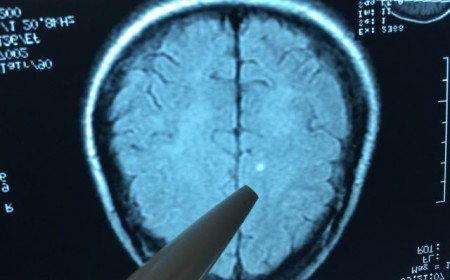

Sán chó cướp đi sinh mạng tràng trai 19 tuổi

Sán chó cướp đi sinh mạng tràng trai 19 tuổi. Bệnh sán chó hiện nay có tỷ lệ dương tính rất cao. Có những địa phương cứ 10 người xét nghiệm thì 3 người nhiễm...